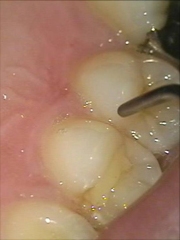

削らない虫歯治療

このくらいの虫歯であれば,無麻酔で治療を行えます。

痛みも音もないので、お子様や歯医者嫌いの方にとてもいい方法です。